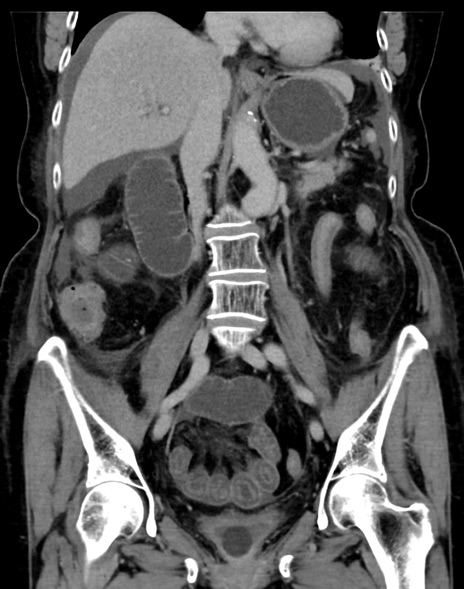

症例13 CT(冠状断像)1日半後